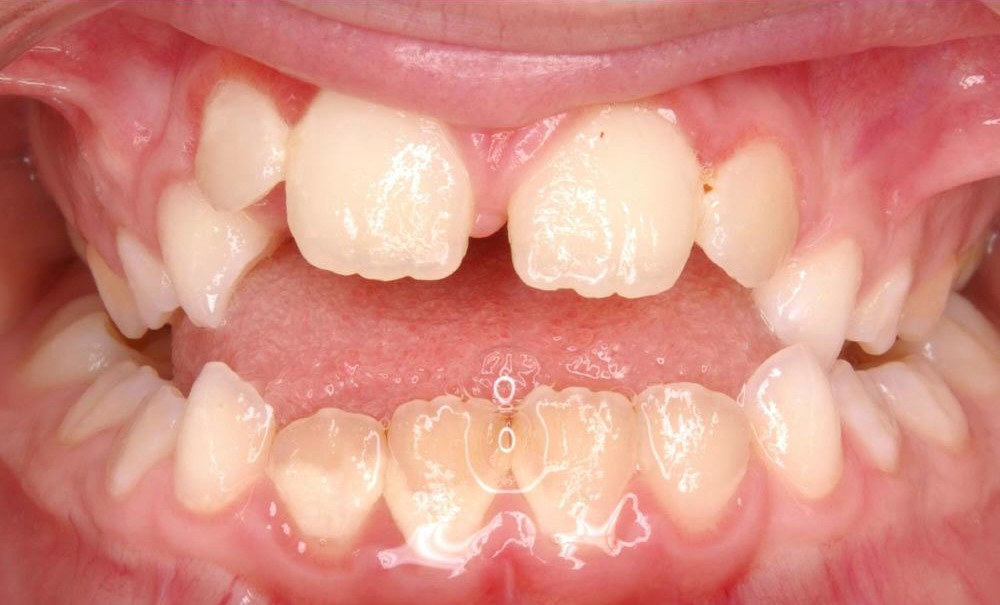

Cette patiente a été suivie dans le cadre d’un traitement interceptif alors qu’elle avait 9 ans. Elle présentait une endognathie maxillaire et une béance antérieure importante liées à des troubles fonctionnels évidents. En effet, l’examen clinique révélait une ventilation buccale exclusive, des ronflements nocturnes et une déglutition atypique. Nous avions noté à l’époque un manque de place pour l’évolution des dents définitives et un inversé d’articulé bilatéral. Les parents avaient rencontré un médecin ORL, mais avaient refusé une intervention visant à enlever les amygdales. Les deux canines maxillaires étaient incluses (fig. 1 à 6).

Quelques années plus tard, au moment de démarrer sa prise en charge orthodontique, la patiente présentait à nouveau une béance antérieure, un décalage des milieux incisifs de 2 mm et le problème transversal avait récidivé. Lors de l’examen clinique, elle présentait un inversé d’occlusion bilatéral postérieur et une ventilation buccale exclusive. À la suite du refus de réaliser l’amygdalectomie de façon précoce, elle ronflait toujours et sa déglutition ne s’était pas modifiée malgré des séances d’orthophonie (fig. 7 à 15).